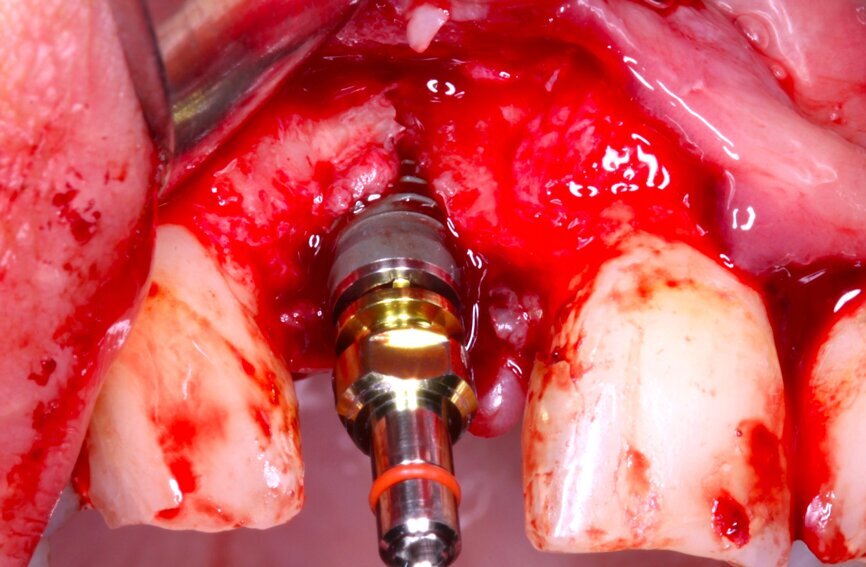

Fig. 10 Figura 10

1. Inserción del implante, con una estabilidad primaria correcta y posición prostodóntica ideal.

2. Realización de perforaciones en el lecho con fresa redonda para aumentar la disponibilidad de células osteogénicas y acelerar la revascularización y mejorar la unión injerto huésped.